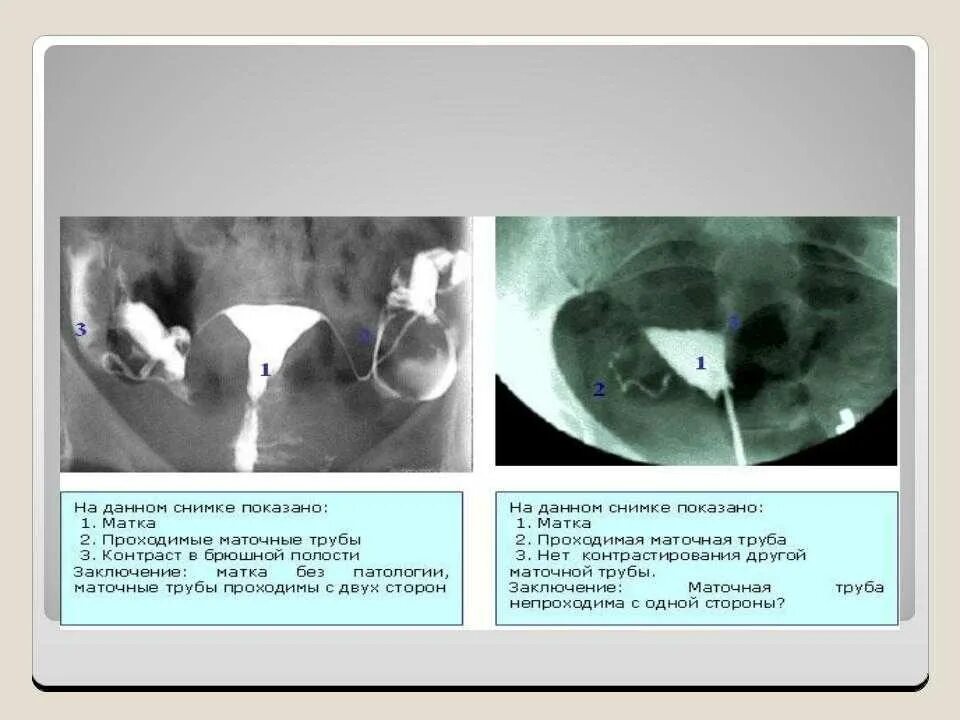

Можно развязать трубы и забеременеть